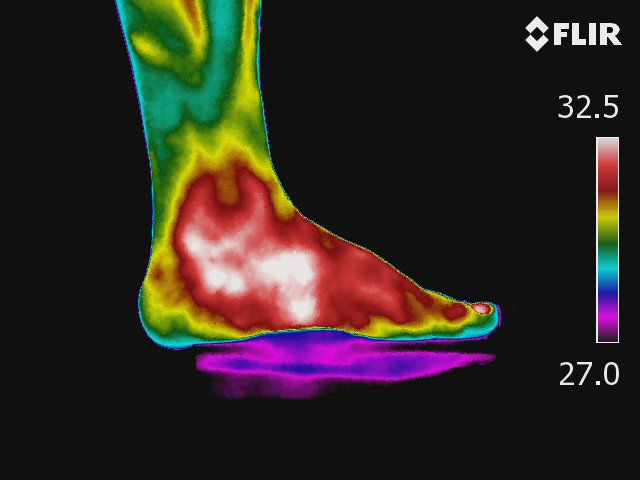

Vasculites - Inflamação das artérias e veias.

Fenômeno presente em quase todas as doenças reumáticas.

Anexo a termografia da rede microcirculatória da artéria tibial posterior em paciente portadora de psoríase.